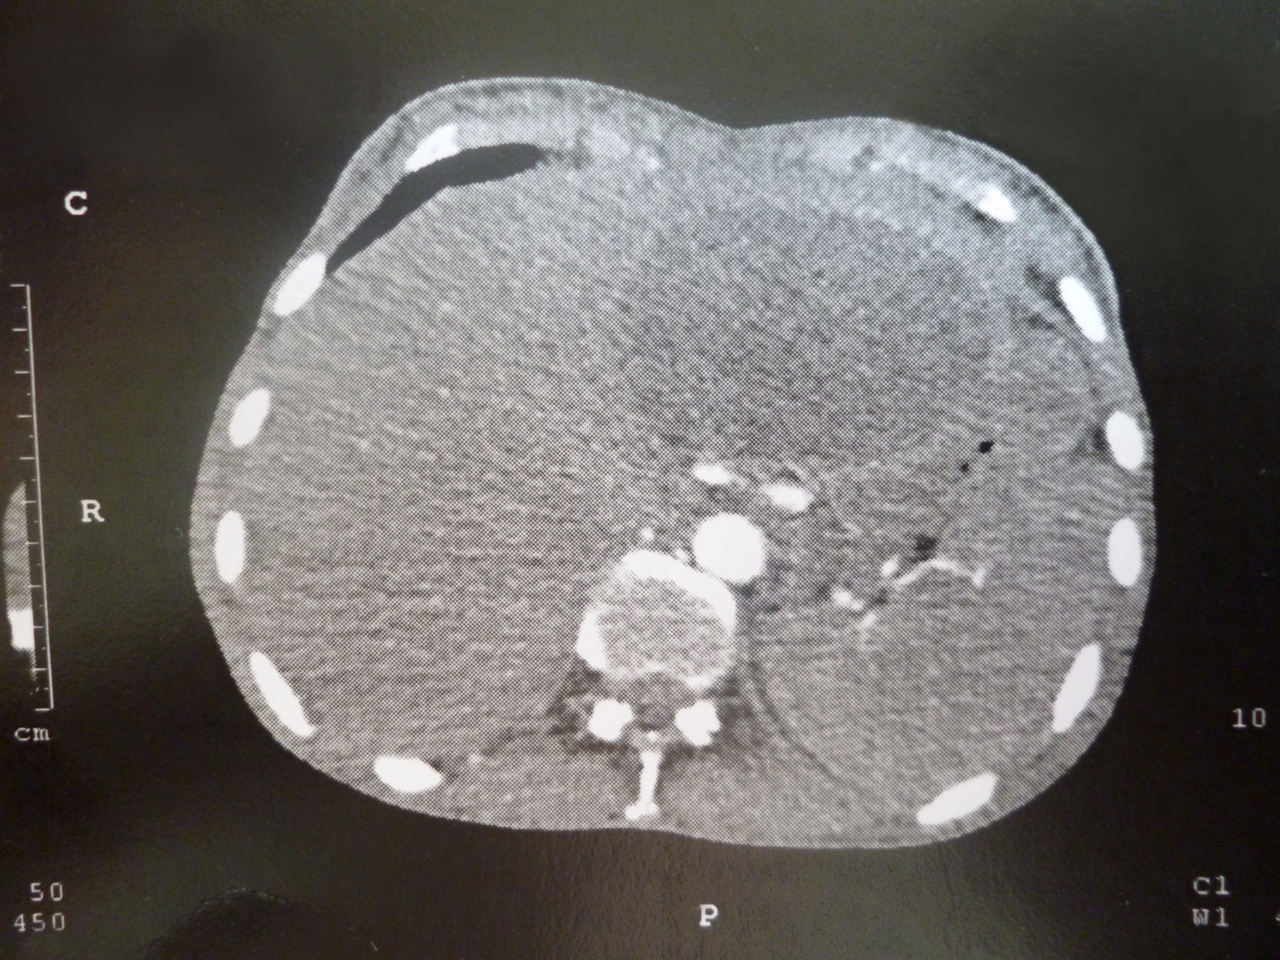

Quel est votre diagnostic ?

Il s'agit d'un kyste hydatique.

Cette photo provient de la collection du Pr Olivier Fain (CHU Jean Verdier, Bondy).